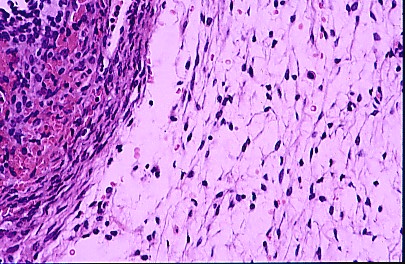

Figura 7

La Figura 7 muestra a mayor aumento a la izquierda el tejido subalbugineo conservado y el edema del estroma a la derecha. H y E x200.